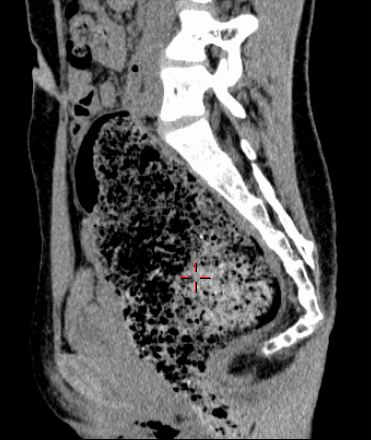

腹盆腔CT上显著扩张的直肠

在小娜的腹盆腔CT报告中,显示出明显的直肠扩展现象。这一异常表现引起了医生的重视。为此,王楠楠会同放射科、外科等专家对小娜进行了会诊,最终诊断其患有“脊髓栓系综合征”。